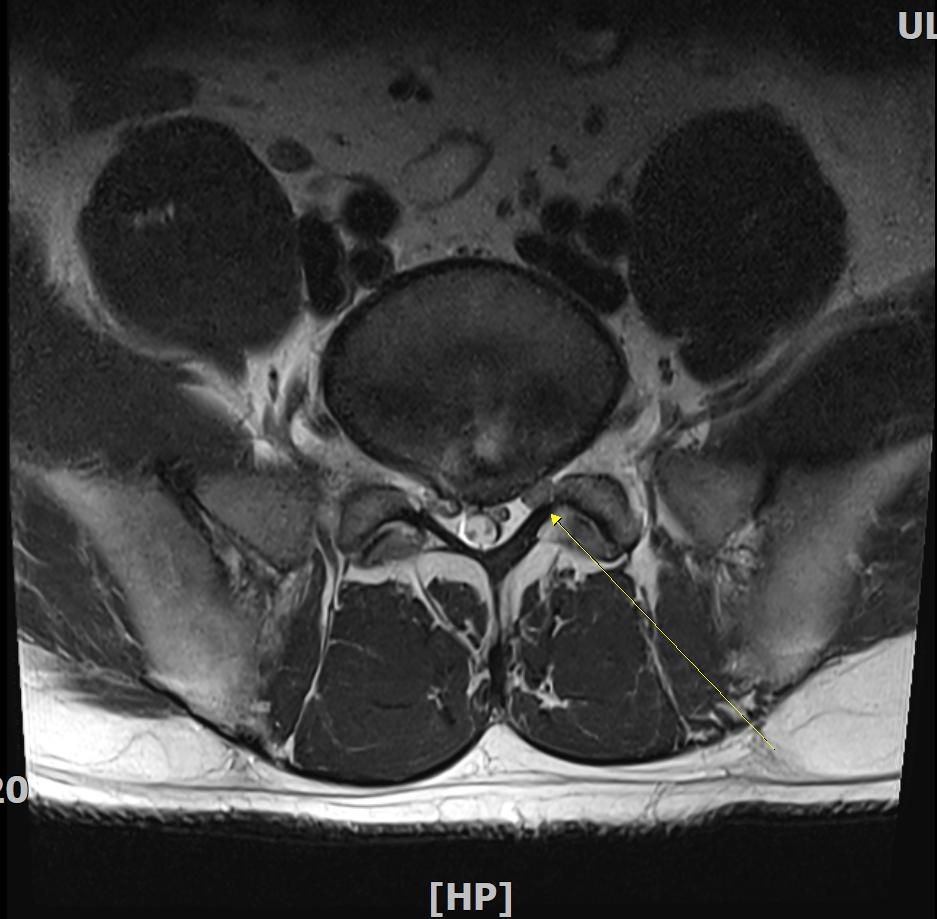

판독부탁드립니다. L4-5번 후궁절제술 및 디스크 제거술 2004년도에 실시하였으며 금번 mri상 추간판탈출증소견 받았습니다. 재발인지 궁금합니다

20년전 수술로 인하여 신경손상이 의심되는데 현재 하지방사통 및 종아리 발가락 등 오래 걷지못하고 일상생활에 지장이 옵니다. 감사합니다

• 1번 째 사진

근전도 검사 결과 요추 5번 신경뿌리병증이 보인다는 내용입니다. 재발이라고 단언할 수는 없으나 과거 수술한 위치와 동일한 것으로 추정됩니다. 잘 치료하여 회복되시길 바랍니다.